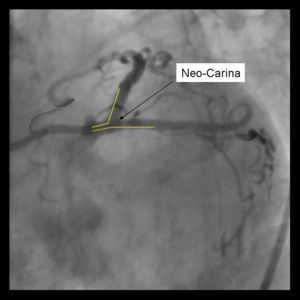

Un-endothelialized layer of stents forming neo-carina may predispose to stent thrombosis. 8Fr Guide system required May be difficult to re-access side branch or parent vessel